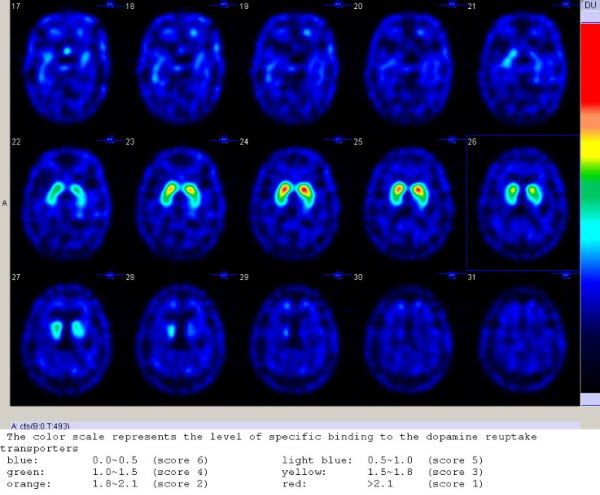

多巴胺造影之判讀

在正常人可見基底核有顯著的造影劑攝取,惟該攝取值會隨年齡的增長而呈下降趨勢。本院神經科醫師針對上百位男女各半,不同年齡層、不同發病期及不同嚴重度的帕金森氏病病友進行研究。發現帕金森氏病病患基底核鎝-99m TRODAT-1的攝取量比正常人少。同時,隨著病情嚴重度越大,鎝-99m TRODAT-1攝取量的下降程度也越明顯。由此,該造影劑在基底核攝取量之變化,也可視為區分病情嚴重度的一個生化指標。為獲取更專業的檢查報告結果,本項檢查報告在北院區長庚醫院由核子醫學科/神經內科專科醫師共同判讀。

下圖為典型的正常受試者的多巴胺掃描影像。以腦部橫切面斷層作呈現供醫師判讀,中間一排有兩個豆狀對稱紅色物體為腦中紋狀體(又稱為基底核),該結構會聚集豐富的多巴胺神經,多巴胺追蹤劑 (TRODAT) 會聚集在該結構,若神經元數量正常則呈現紅色顯影,表示多巴胺神經元沒有缺損。

多巴胺神經退化所致的帕金森氏病,其病理特徵是由單側開始的多巴胺神經元退化,且該退化順序從紋狀體的豆狀尾部開始往頭部發展,所以多巴胺影像可見紋狀體 TRODAT 分布不對稱下降 (紋狀體的顏色呈現黃綠色或藍色),且下降嚴重程度在豆狀尾側 (顏色呈現藍色) 較頭側 (顏色呈現黃綠色) 明顯。如下圖。